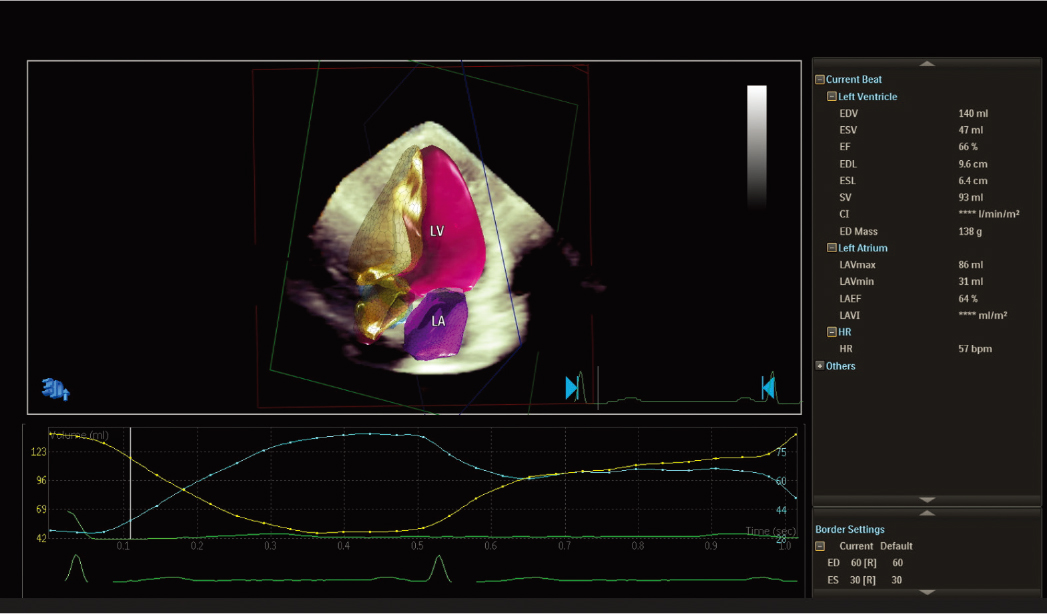

现配备 2D 自动 EF 和中间层应变 Advances 的进步之处在于,它能够在同一应用程序中提供快速、可重复的结果,作为全面 LV 评估的一部分,从而改善工作流程并节省时间。 | ![]() 自动节段性室壁运动评分* 在标准 17 段靶心显示屏上自动评估壁运动,以帮助客观评估 LV 壁。 |

![]() 3D 自动彩色血流定量* 提供 AI 来快速、简单且可重复地测量二尖瓣反流 (MR) 体积,以帮助评估 MR 严重程度。 | ![]() 3D 自动三尖瓣定量* 人工智能通过精确的术中TV环测量(初始尺寸确定和CT计划)帮助确认/重新评估设备尺寸/选择。 |